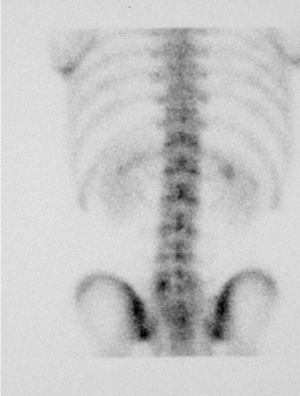

A los 15 días el paciente se presenta con sintomatología atenuada. La GOP/SPECT (figs. 4 y 5) demuestra fenómenos de remodelación ósea a nivel de ambas pars de L5. Por tanto, se concluye el diagnóstico de espondilólisis activa L5 derecha y espondilólisis izquierda en formación. Se continúa el mismo tratamiento agregándose una pauta específica de ejercicios delordosantes y ortesis plantares de corrección.

Figura 4

Figura 5